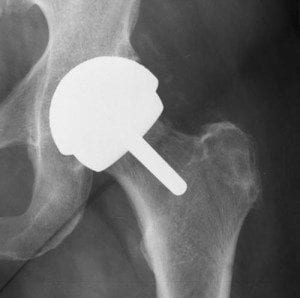

Metal-on-metal hip implant concerns have gotten the FDA’s attention. The agency announced in December 2017 that metal-on-metal (MoM) hip implants carry unique risks, in addition to the general risks of all hip implants.The metal ball and metal cup in MoM hip implants slide against each other while an implantee is walking, sitting, or running. When metal from the two parts rubs together, tiny particles can wear off of the ball and cup, moving around or between them.

The FDA notes that wear and corrosion at the connection between the metal ball and taper of the stem may also occur. Some of the metal ions – such as cobalt and chromium – from the metal implant or from the metal particles will enter the bloodstream, according to the FDA.

To optimize the way in which the ball and socket rub against each other, the FDA says orthopaedic surgeons take several precautions before and during hip replacement surgery. The idea is to produce and release as few metal particles as possible, but therein lies the problem. There is simply no way to fully avoid the production and release of some metal particles.

Metal particles around some implants can eventually damage bone and/or tissue surrounding the implant and joint. An “adverse local tissue reaction (ALTR)” or an “adverse reaction to metal debris (ARMD)” can cause soft tissue damage. Such damage may lead to pain, implant loosening, device failure, and replacement surgery. The agency says, “Patients with a progressing ALTR may be considered for earlier revision to prevent extensive damage to bone, muscle and nerves.”